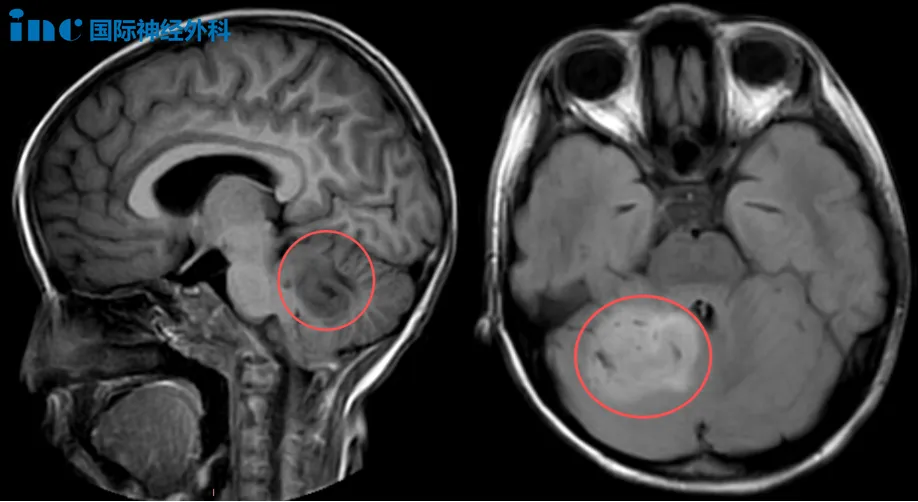

6岁女儿小脑巨瘤

和巴爷爷面对面交流后,我们决定手术!

几天前,女孩乐乐在放学回家后,向父母抱怨起自己白天有些头晕疲乏,没想到又出现呕吐。父母急忙将她送至医院检查,没想到,这彻底改变了一家人安稳平静的生活。进一步检查乐乐被诊断为“小脑占位性病变”,考虑低级别胶质瘤。3天时间,乐乐多次呕吐、头晕、恶心,父母心急如焚。尽管住院一段时间后,乐乐的头晕症状和精神状态均有所好转,但脑袋中的肿瘤却始终令一家人如鲠在喉,是他们心中不得不拔掉的一根刺。和教授面对面交流后,当得到可以手术的评估后,他们便下定决心要找巴教授手术。

6岁男孩脑桥-桥臂占位性病变

“我脑子里有虫子在爬。”当年幼的佑佑说出这句话时,这并非童言无忌的想象,而是大脑发出的求救信号。今年9月,佑佑突然出现四肢不自主运动、摇头、伸舌头等现象。当父母带着他前往医院就诊时,佑佑说经常头晕,自觉脑内有虫子。进一步检查发现,四脑室内异常信号,大小约14*13*9mm,考虑低级别胶质瘤。“不保证能全切”深深困扰着夫妻两,不能全切如果再复发,孩子该怎么办?

巴教授可以为孩子全切肿瘤吗?带着期望,他们找到巴教授。好在发现及时,病灶还不大,且没有侵袭脑干,巴教授评估有全切的机会。